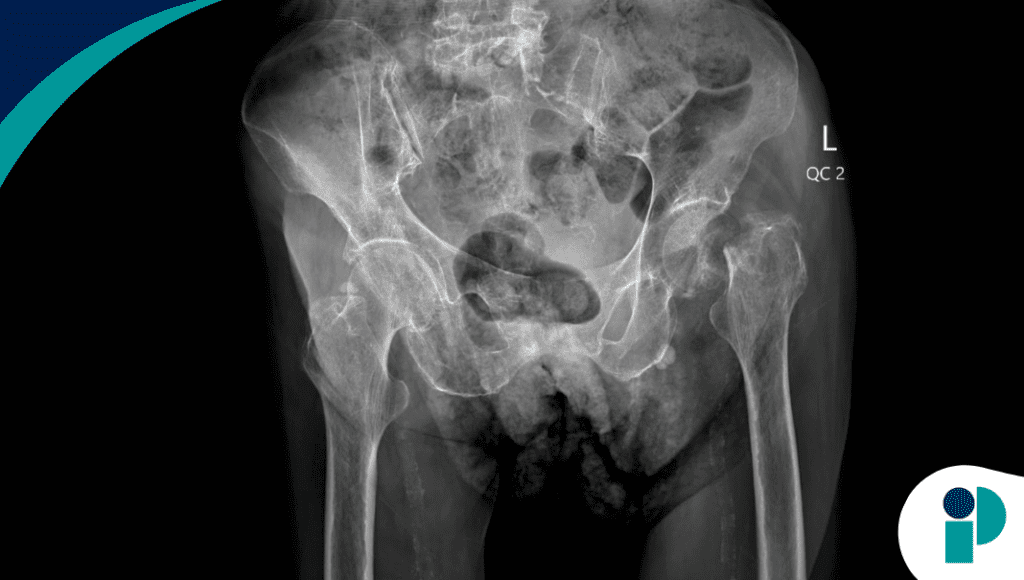

Durante siete años, un hombre de poco más de 60 años perdió fuerza hasta quedar prácticamente postrado, sin saber que tenía fracturas bilaterales del cuello femoral y 11 costillas rotas. El responsable no era la neuropatía ni la enfermedad de Lyme como le habían dicho, sino un diminuto tumor de 15 x 9 mm incrustado en su fémur izquierdo.

Los laboratorios mostraron hipofosfatemia severa, vitamina D activa baja y niveles elevados de FGF23, la hormona responsable de aumentar la pérdida renal de fosfato. Esa combinación clásica apuntó a osteomalacia inducida por tumor, una condición rara que puede pasar inadvertida porque el fósforo sérico no siempre se mide de rutina.

La PET/CT con cobre-64 DOTATATE detectó captación en el cuello femoral izquierdo. El muestreo venoso confirmó que allí estaba la fuente de FGF23. Tras la resección del tumor y artroplastia total de cadera, los niveles bioquímicos se normalizaron en una semana.